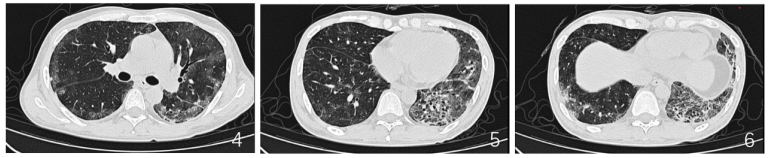

血气分析:pH 7.461,PaCO2 37.2 mmHg,PaO98.0 mmHg,实际碳酸氢根26.9 mmol/L;PaO2/FiO2 288.3 mmHg(FiO2 35%)。11月8日复查胸部CT:考虑双肺间质性肺炎可能(图2

图片

患者2022年11月8日复查胸部CT

特殊染色:PAS染色(-),六胺银染色(-),抗酸染色(-)。完善BALF NGS:细环病毒(序列数260),肝炎GB病毒C型(序列数590)。血NGS:肝炎GB病毒C型(序列数604350)。鼻咽拭子NGS:肺炎克雷伯菌(序列数11933),鲍曼不动杆菌(序列数61)。患者于11月12日复查胸部CT:双肺多发感染较前明显吸收(图3

3  患者2022年11月12日复查胸部CT,对比11月8日明显吸收